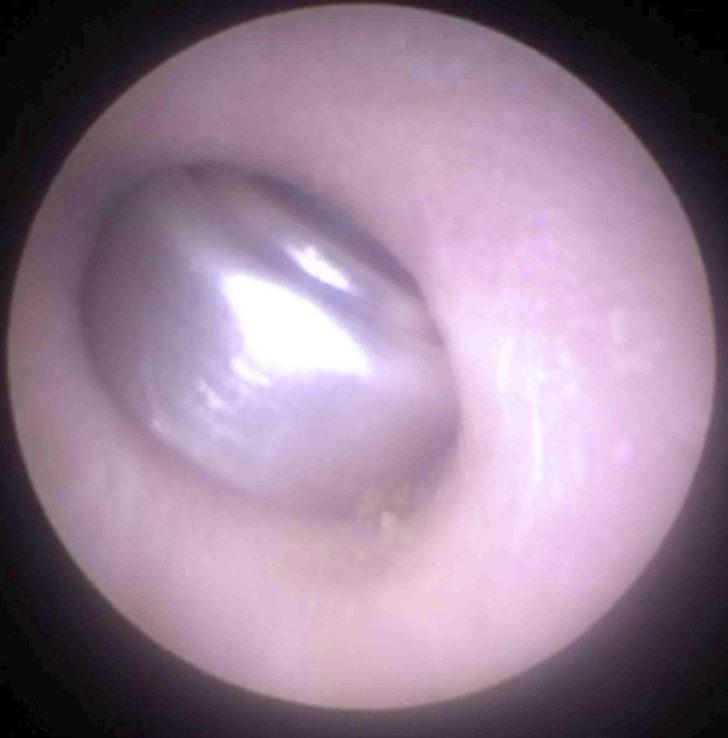

Mr. Neel Raithatha ise bu durum karşısında ilk olarak 4 mm'lik bir endoskopi aleti kullanmayı planlasa da kulak çapı için uygun olmayacağından bu kararından vazgeçerek bir mıktasından tardım alıyor.

İşitme cihazı pilinin bulunduğu noktayı bir kamera yardımıyla teşhis eden Mr. Neel Raithatha, ardından mıknatısı pile yaklaştırdı.